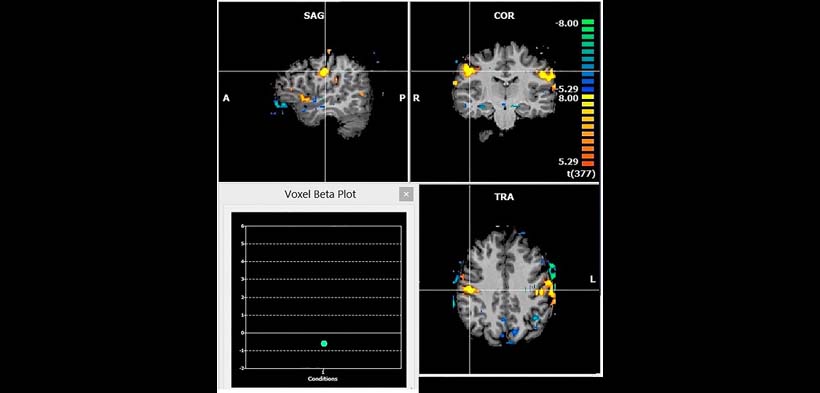

Fig. 1. RMF de un paciente con diagnóstico de bruxismo. Se evidencia las diferencias de señal entre el descanso y períodos de actividad de apretamiento. Zonas amarillas muestran aumento de activaciones durante el apretamiento de los dientes. Estas áreas están de acuerdo con las áreas de la masticaciónl. A, anterior; COR, coronal; L, izquierda; P, posterior; R, a la derecha; SAG, sagital; TRA, transversal.